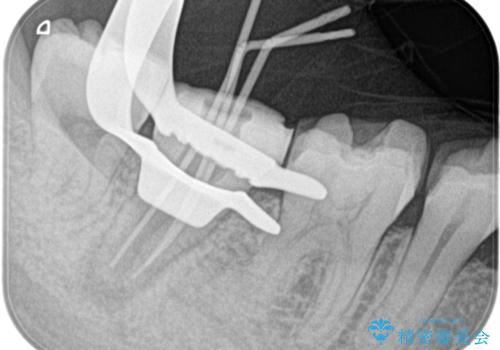

- 定期検診にて膿の出口を見つけたことを主訴に来院されました。

検査の結果、診断を歯髄壊死、症候性根尖性歯周炎とし抜髄を行っております。

根管充填はCWCTにて行なっています。